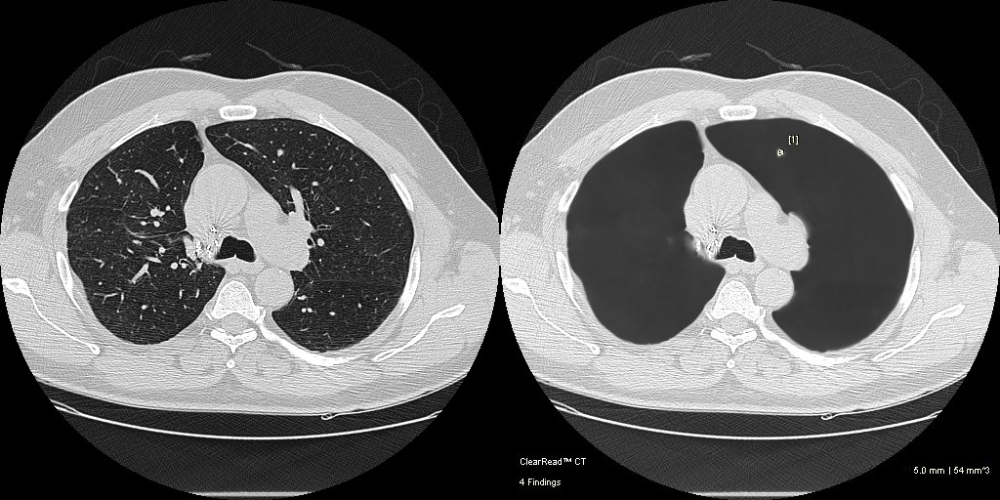

Pulmonary Nodules Automated nodule analysis, current and prior, and reporting to lighten cognitive load

- Fully-automatic nodule detection and analysis

- Quickly & easily compare nodule findings with prior exams – monitor changes in volume, diameter, and doubling time

- 36% faster reads1 and 29% fewer missed nodules2